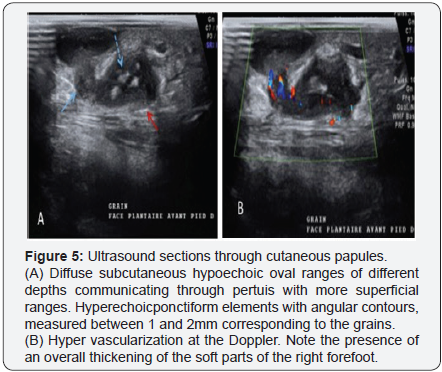

Doppler ultrasound (realized for free) performed in projection of the plantar face of the right foot, visualized opposite the cutaneous papules, hypoechoic oval beaches. They had different depth levels in the subcutaneous tissue. The deepest ones communicated by pertuis with the more superficial beaches. Within certain deep collections, spontaneously hyperechoic elements with angular contours, measured between 1 and 2mm corresponding to the grains, were visualized. At the Doppler, there is an arterial hyper-vascularization within hypoechogenic rearrangements (Figure 5). An overall thickening of the soft parts of the right forefoot was noted. These subcutaneous hypoechoic formations on the plantar surface of the right foot containing hyperechogenic grains in them, are compatible with a fungic ultrasound. Doppler hypervascularization may reflect the presence of active inflammatory remodeling.